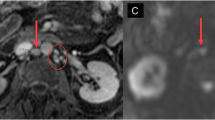

We examined the role of total body magnetic resonance imaging (TB-MRI)-governed involved compartment irradiation (ICI) and high-dose chemotherapy (HDC), followed by stem cell rescue (SCR) in patients with high-risk Ewing tumors (ETs) with multiple primary bone metastases (high-risk ET-MBM). Eleven patients with high-risk ET-MBM receiving initial assessment of involved bones by TB-MRI were registered from 1995 to 2000 (group A). In all, 6 patients out of 11 had additional lung disease at initial diagnosis; all had multifocal bone disease with more than three bones involved. After systemic induction with etoposide, vincristine, adriamycin (doxorubicin), ifosfamide, and actinomycin D (EVAIA) or VAIA chemotherapy, ICI of all sites positive by TB-MRI was administered, followed by HDC and SCR. A second group matched for observation period and consisting of 26 patients with more than three involved bones at diagnosis was treated with the European Intergroup Cooperative Ewing Sarcoma Study-92 (EICESS-92) protocol (group B). These patients did not receive TB-MRI and consequently did not receive TB-MRI-governed ICI, or HDC and SCR. Survival in group A vs group B was 45 vs 8% at 5 years and 27 vs 8% at 10 years after diagnosis (log rank and Breslow: P<0.005). We conclude that TB-MRI-governed ICI followed by HDC and SCR in ET-MBM is feasible and warrants further evaluation in prospective studies.

Daldrup-Link HE, Franzius C, Link TM, Laukamp D, Sciuk J, Jurgens H et al. Whole-body MR imaging for detection of bone metastases in children and young adults: comparison with skeletal scintigraphy and FDG PET. Am J Roentgenol 2001; 177: 229–236.

Steinborn MM, Heuck AF, Tiling R, Bruegel M, Gauger L, Reiser MF . Whole-body bone marrow MRI in patients with metastatic disease to the skeletal system. J Comput Assist Tomogr 1999; 23: 123–129.